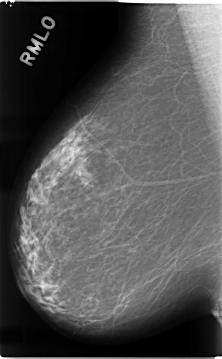

C_0112_1.RIGHT_MLO

C_0112_1.LEFT_MLO

LEFT_MLO LINES 4720 PIXELS_PER_LINE 2872 BITS_PER_PIXEL 12 RESOLUTION 50 OVERLAY

RIGHT_MLO LINES 4664 PIXELS_PER_LINE 2880 BITS_PER_PIXEL 12 RESOLUTION 50 NON_OVERLAY